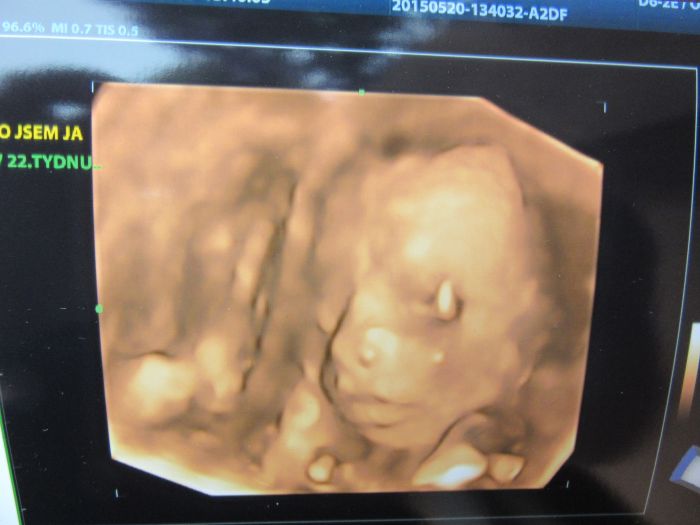

Ahojky, tak dneska jsme byli s manželem na 3D a máme potvrzenou malou fešandu. I přesto, že jsme si přáli kluka tak nakonec jsem spokojená, že to bude holčička. Doktor nám taky řekl, že je vše v pořádku a to je to hlavní. Přikládám fotečky, jsem z malý opravdu nadšená.